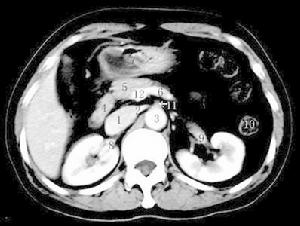

5.血管造影診斷本病的最可靠方法,對疑有本病者行主動脈造影,選擇性腹腔動脈、腸系膜上動脈及腸系膜下動脈造影術,確定血管狹窄閉塞的性質,部位、程度和範圍以及側支循環的建立,應拍側位和前後位片,可顯示明顯的動脈粥樣硬化症及一些血流動力學的改變,在主動脈根部1~2cm內常見動脈硬化病變,常有腸系膜2~3支動脈狹窄或完全閉塞,狹窄程度超過50%,有向腹主動脈的血液反流,同時伴有粗大蜿蜒迂曲的側支供血動脈,有時僅看到1~2主支狹窄但無粗大蜿蜒迂曲的側支血管,仍不能去確定診斷,臨床上血管病變與症狀並非一致,75%的人可有腸系膜動脈硬化的造影表現,值得注意的是,無症狀的老年人在腸系膜血管造影時10%~20%有明顯病變。